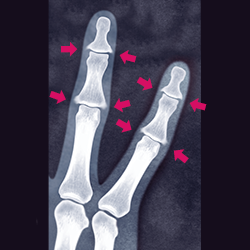

<X線検査>

X線検査は最もよく用いられている画像検査です。X線検査では骨の破壊、骨の新たな形成、関節の変形などがわかります。早い段階での関節の変化などはわからないため、早期診断には不向きです。

イメージ:X線検査